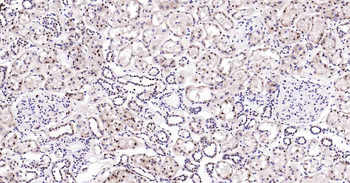

50 μl, 100 μl - KLF4 Recombinant Rabbit Monoclonal Antibody [orb608075]Featured

FC, ICC, IF, IHC-Fr, IHC-P, WB

Human, Mouse, Rat

Rat

Rabbit

Recombinant

Unconjugated

200 μl, 50 μl, 100 μl - Featured